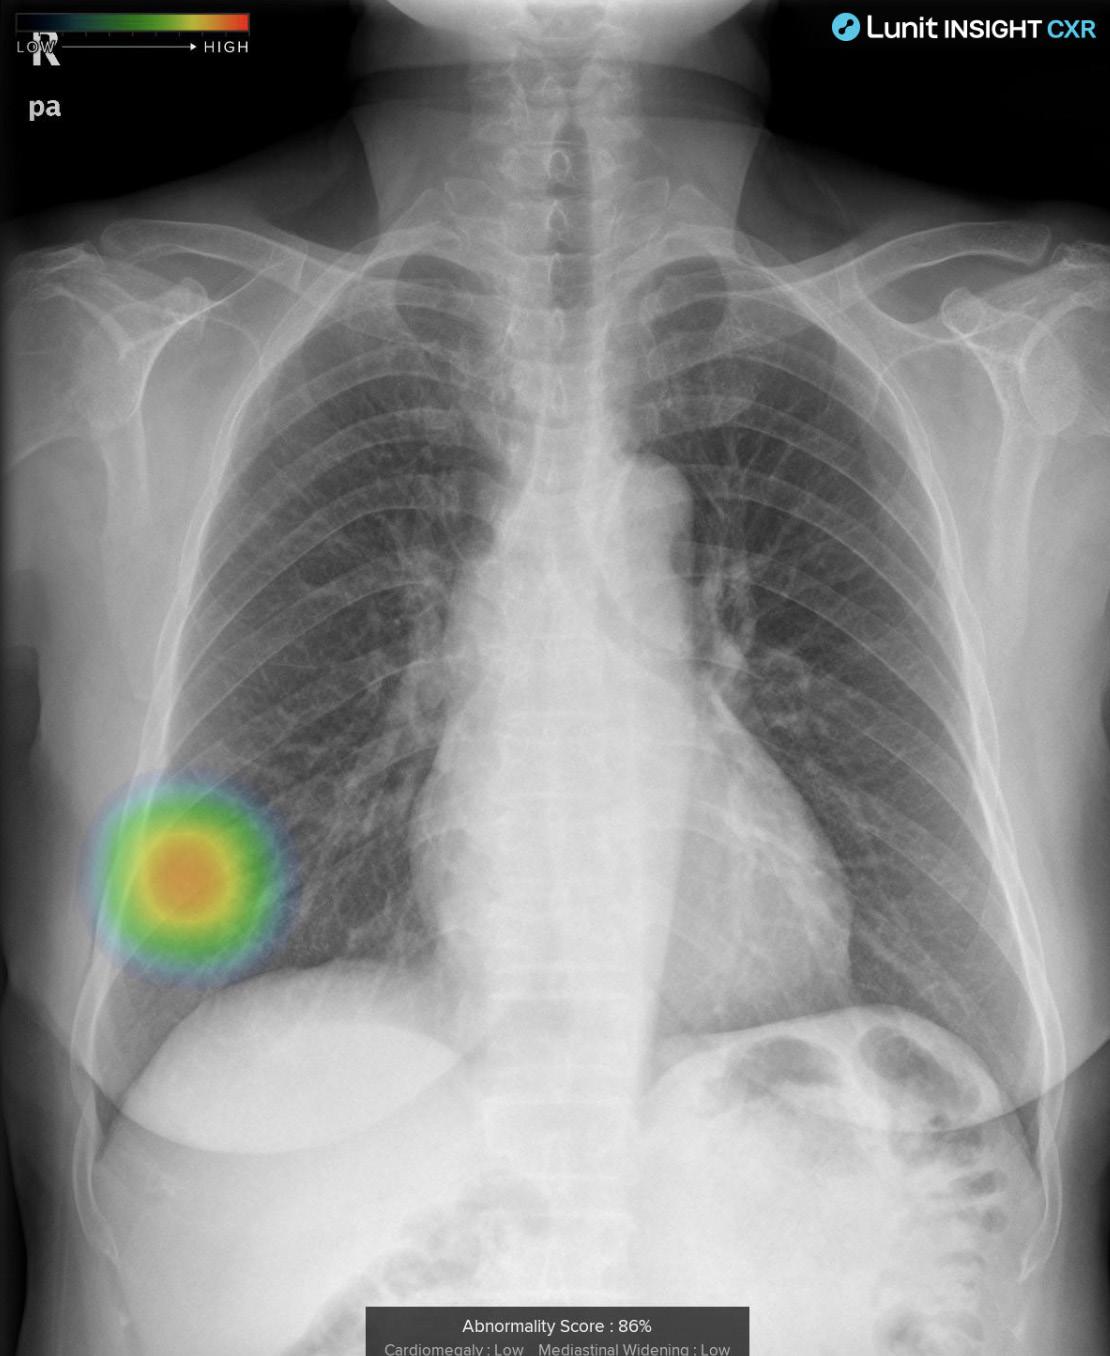

Lunit: Revolucionando la Radiología con Inteligencia Artificial

Desde el corazón del Congreso Europeo de Radiología en Viena, tuvimos el privilegio de entrevistar a Stefan Mercurio, responsable de Europa del Sur en Lunit, una empresa coreana líder en inteligencia artificial aplicada a la radiología.

Una de las principales aplicaciones desarrolladas por Lunit es Insight CXR, diseñada para la interpretación automatizada de radiografías de tórax. "Con Insight CXR, podemos detectar más de 10 anomalías comunes, como nódulos, consolidaciones y neumotórax, con una precisión asombrosa", explicó Mercurio. "Esto es especialmente crucial en entornos de emergencia, donde cada minuto cuenta y los médicos deben tomar decisiones rápidas y precisas".

El software de Lunit no solo identifica las anomalías, sino que también proporciona una evaluación de la probabilidad de su presencia, lo que ayuda a los médicos a priorizar y planificar el tratamiento de manera más efectiva. "Nuestro software ha sido utilizado en todo el mundo durante la última década, incluyendo países de América Latina como México y Brasil", destacó Mercurio.